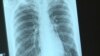

Ровно год назад, во Всемирный день борьбы со СПИДом, ведущий телеканала «Дождь» Павел Лобков в прямом эфире объявил, что инфицирован ВИЧ. Спустя год в интервью Настоящему Времени он рассказывает, какой была реакция общества, и что это такое – жить в России с диагнозом «ВИЧ-положительный»